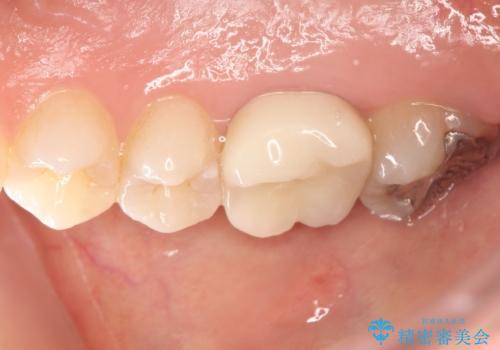

根の神経の治療を行い、セラミックを装着する計画としました。

根の神経が細菌に感染するとこのように、膿の出口ができることがあります。

その場合は、根の中の治療(根管治療)が必要になります。